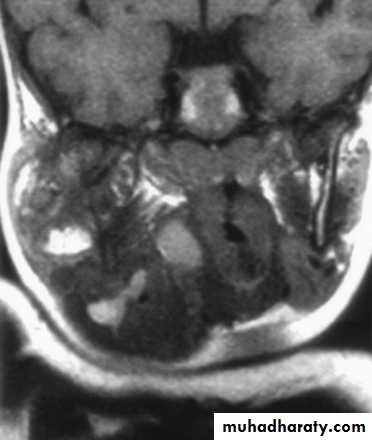

Magnetic Resonance Imaging

Similar information as CT

Better for upper neck and skull base

Vascular delineation with infusion

16

17